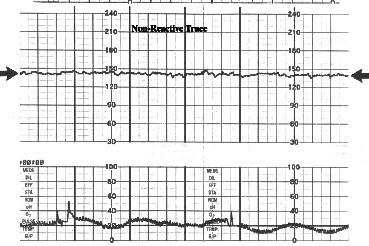

如图有关胎心率的描述不正确的是 ( )A、摆动幅度变动范围正常为5~25bpmB、120bpm

问题 如图有关胎心率的描述不正确的是 ( )

选项 A、摆动幅度变动范围正常为5~25bpm B、120bpm

答案 A